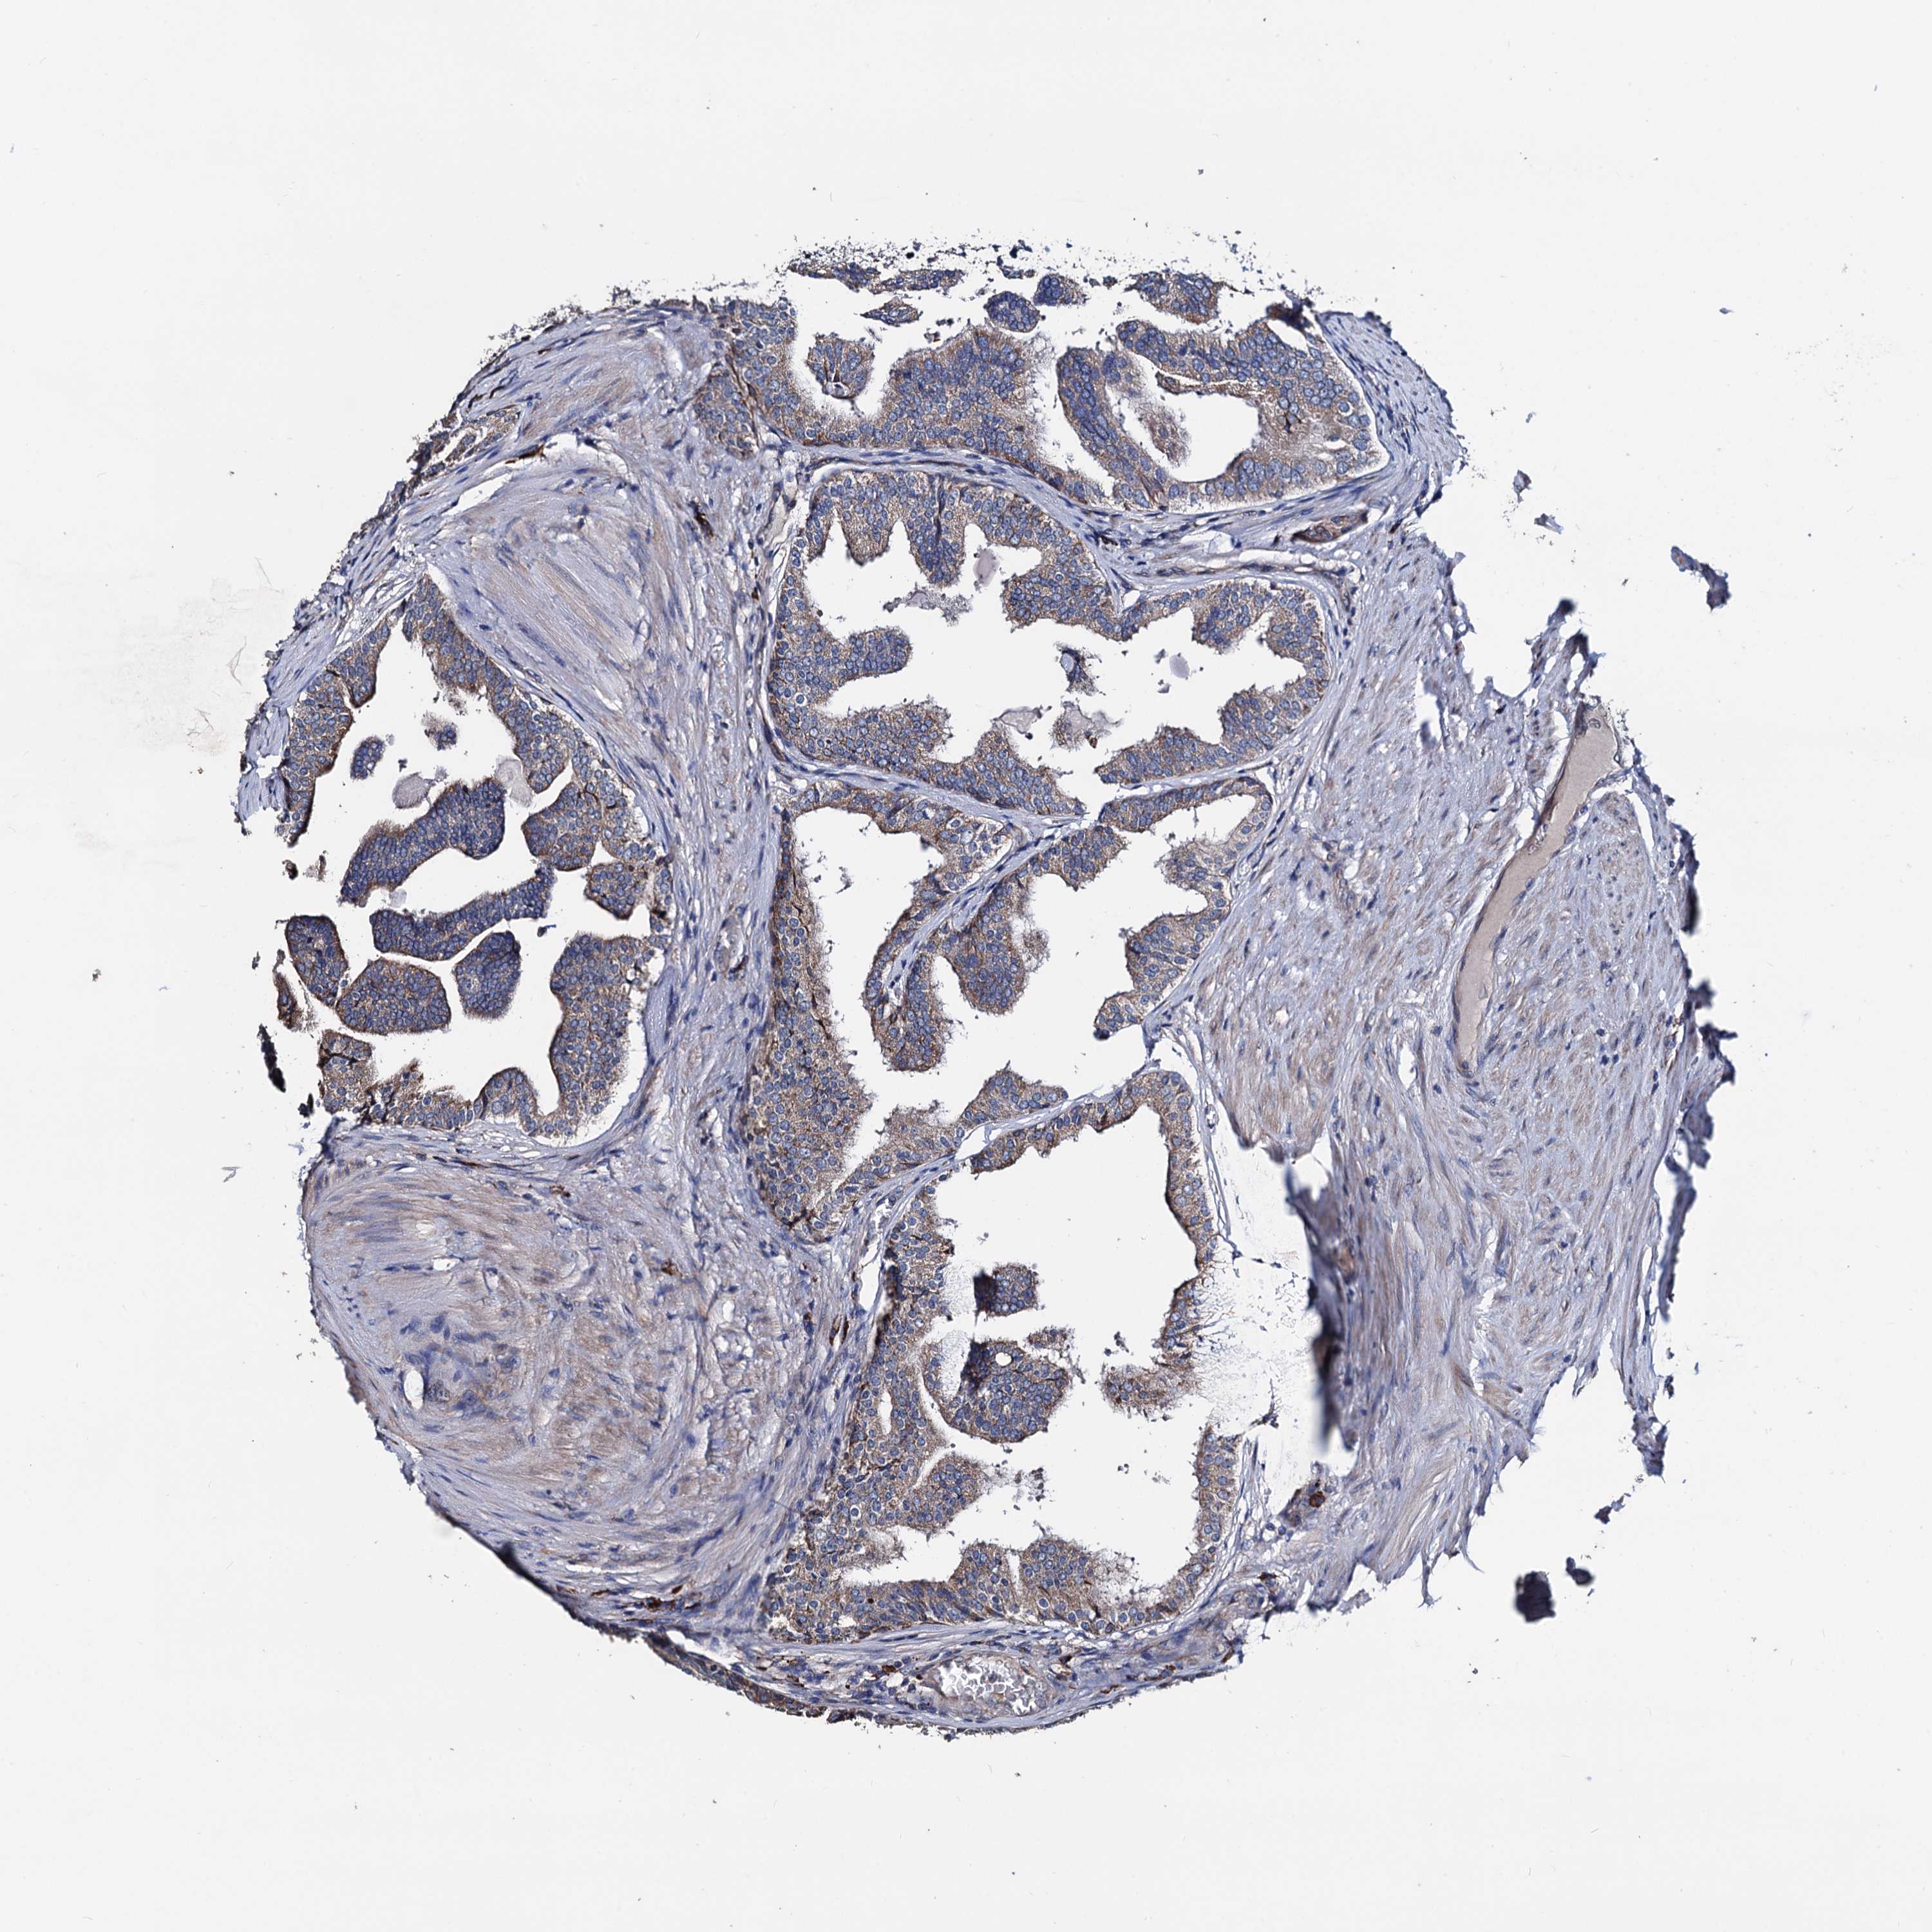

PROSTATE CANCER - Protein expressioni

A mouse-over function shows sample information and annotation data. Click on an image to view it in a full screen mode. Samples can be filtered based on level of antibody staining by selecting one or several of the following categories: high, medium, low and not detected. The assay and annotation is described here.

Note that samples used for immunohistochemistry by the Human Protein Atlas do not correspond to samples in the TCGA dataset.

Antibody stainingi

Antibody staining in the annotated cell types in the current human tissue is reported as not detected, low, medium, or high, based on conventional immunohistochemistry profiling in selected tissues. This score is based on the combination of the staining intensity and fraction of stained cells.

Each image is clickable and will lead to virtual microscopy that enables deeper exploration of all samples and also displays staining intensity scores, fraction scores and subcellular localization as well as patient and tissue information for each sample.

Antibody HPA039089

Staining

High

Medium

Low

Not detected

Intensity

Strong

Moderate

Weak

Negative

Quantity

>75%

75%-25%

<25%

None

Location

Nuclear

Cytoplasmic/membranous

Cytoplasmic/membranous,nuclear

Adenocarcinoma, NOS

Adenocarcinoma, High grade

Adenocarcinoma, Low grade